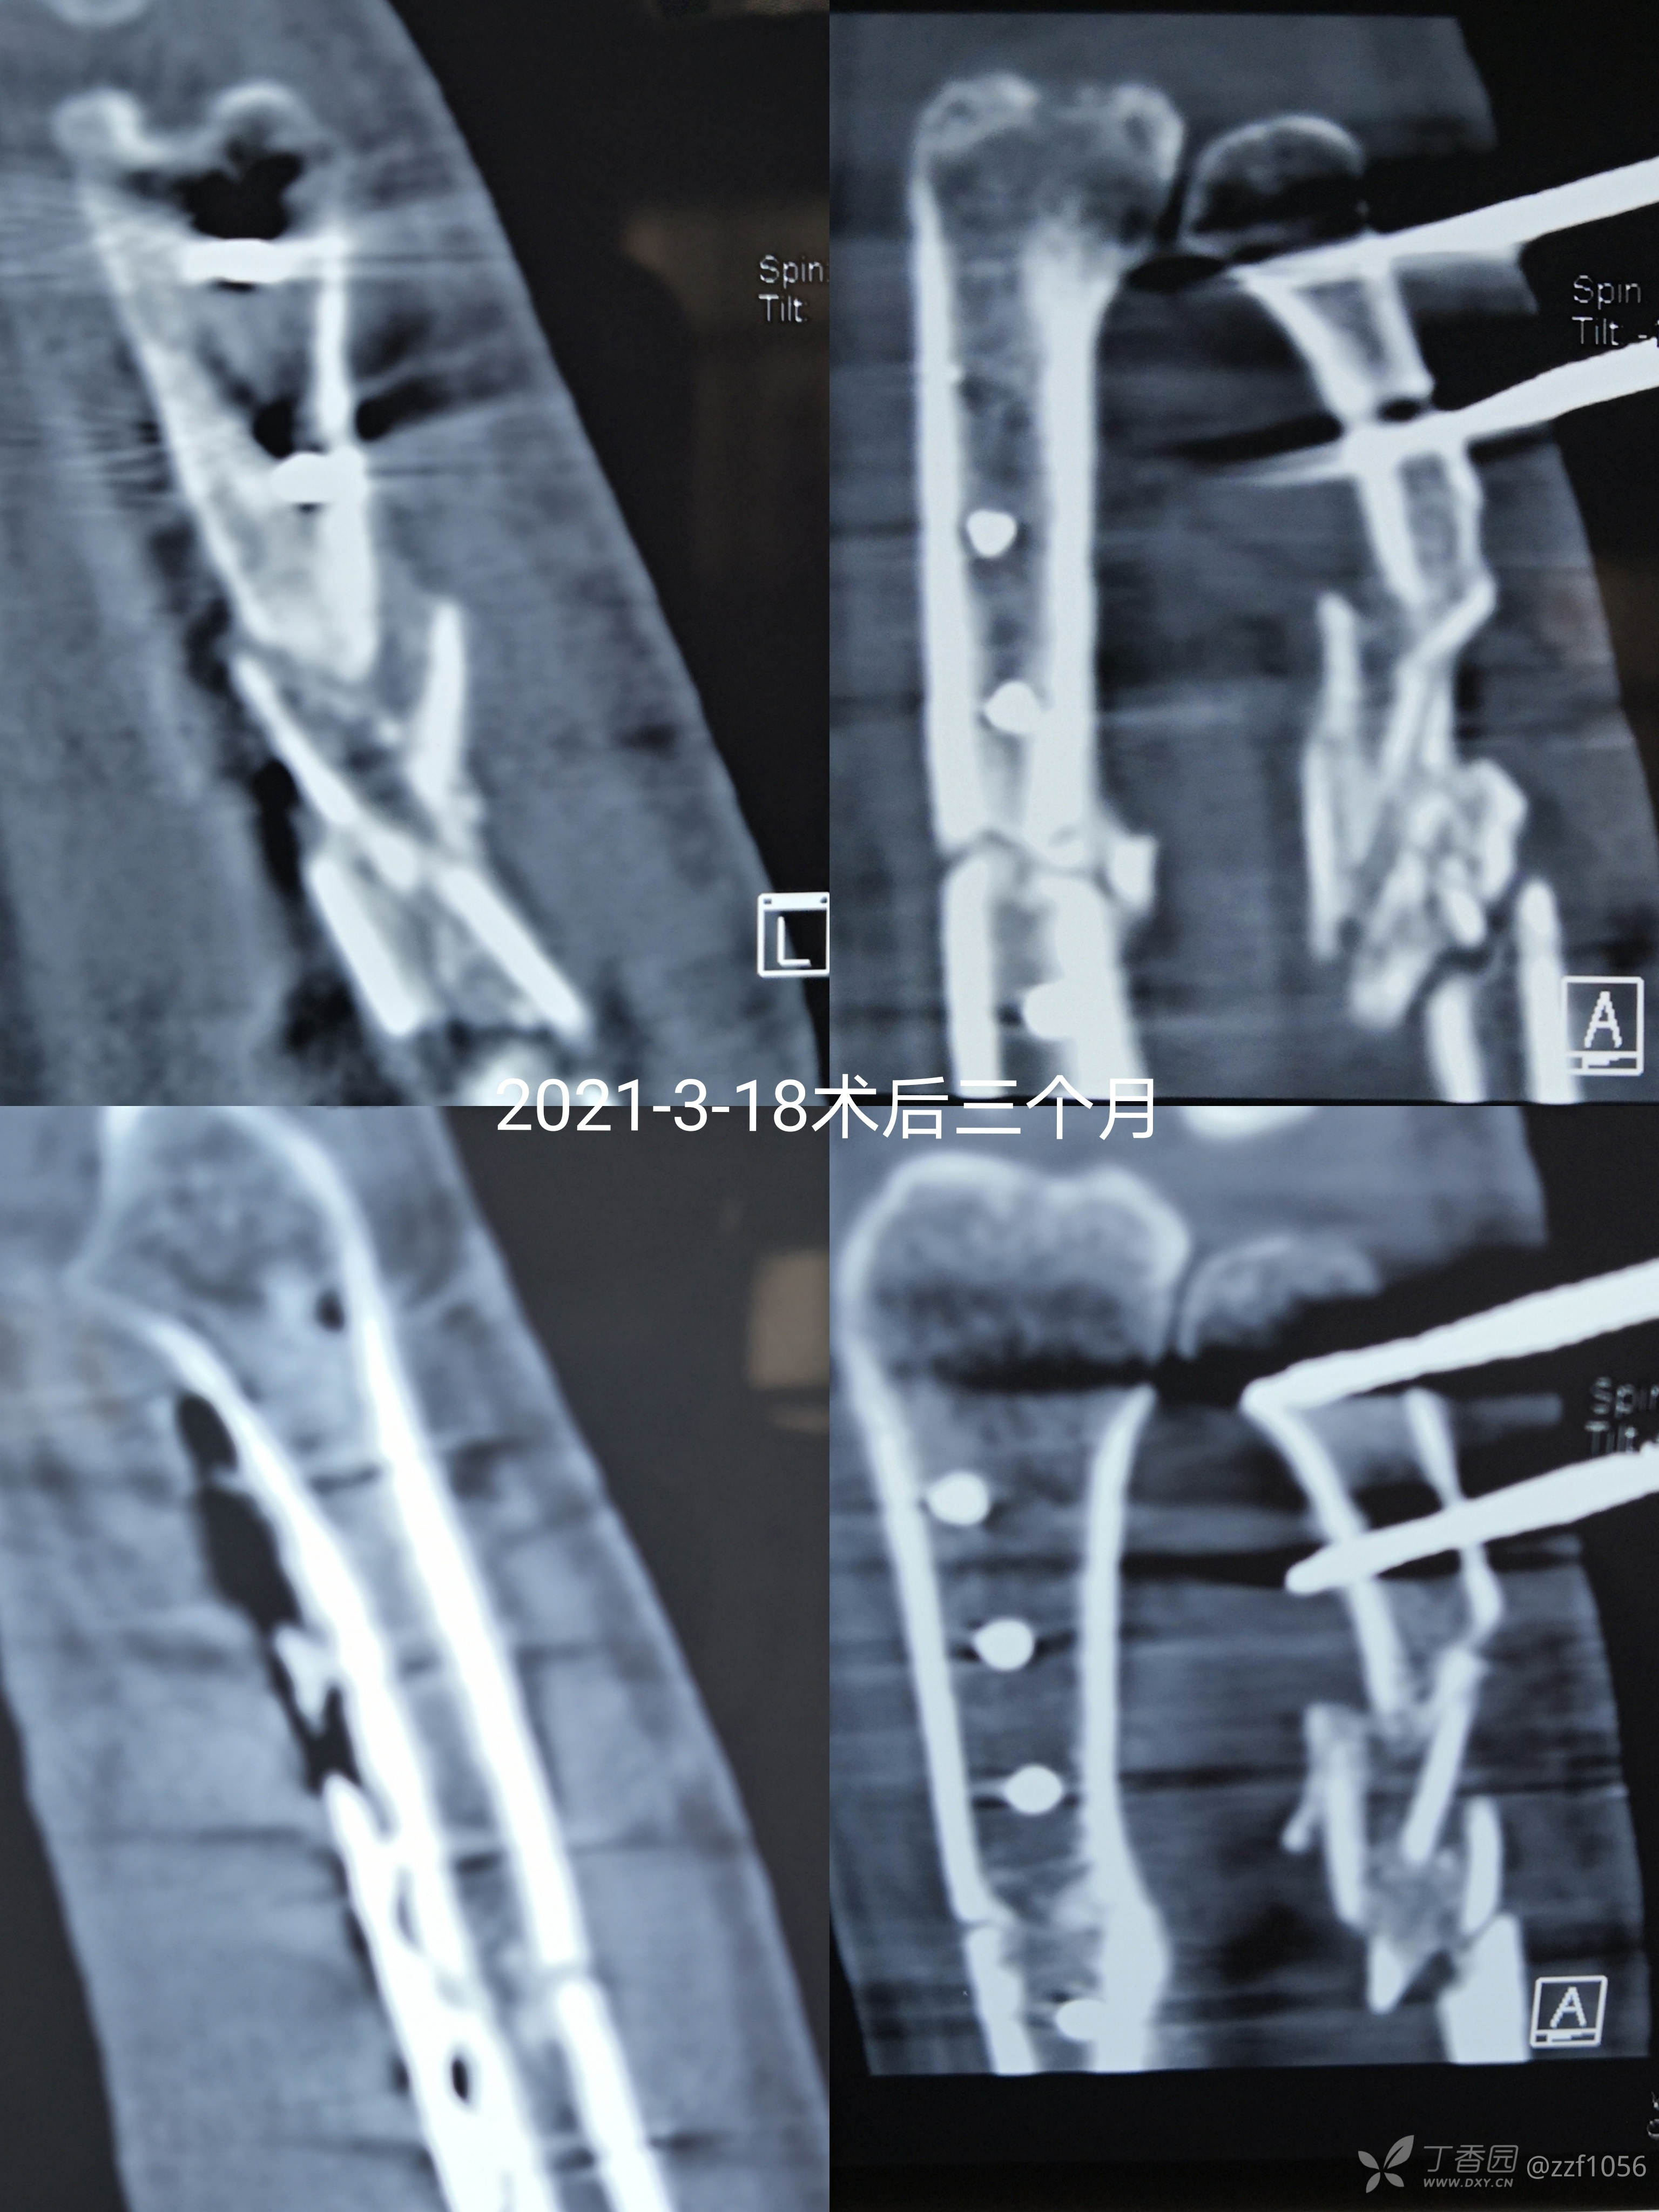

术后三个月

交代再观察两个月去架